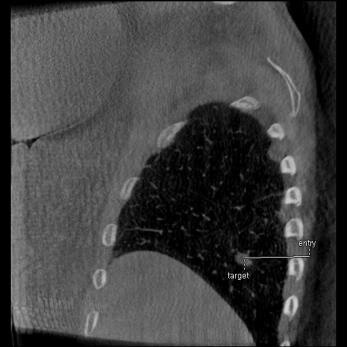

INTERVENTIONS AU NIVEAU DU RACHIS

Guider